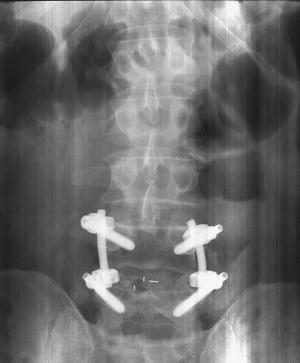

During the 6 1/2-hour operation, the doctor made a 12-in. incision in my back, cutting away all the "unnecessary" bone around the vertebrae and also removing the soft disc between the two vertebrae. Then he packed the open area with my own ground-up bone which had been mixed with a special protein that makes it grow. He then inserted four large titanium "lag bolts" and two rods to secure the two vertebrae while the bone "grows" and hardens. Once the fusion hardens û it takes about 6 months û the metal hardware will serve no purpose. However, they generally don't take them out because they're buried under layers of skin and muscle. I can't even feel them.